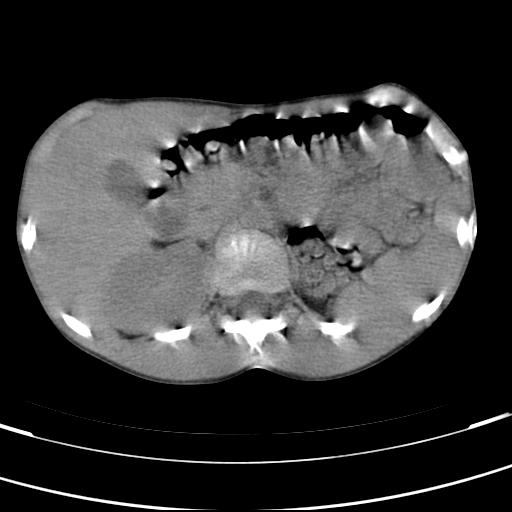

标题: PED3157:左肾缺如,请教脾脏的改变?、、

男孩,9岁。胃部不适。

脾脏位于左侧,但数个脾脏呈分离状态,左肾缺如,右肾代偿肥大。考虑多脾综合征。